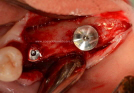

Clinical Cases

• Case1

• Case2

• Case3

• Case4

• Case5

• Case6

• Case7

• Case8

• Case9

• Case10